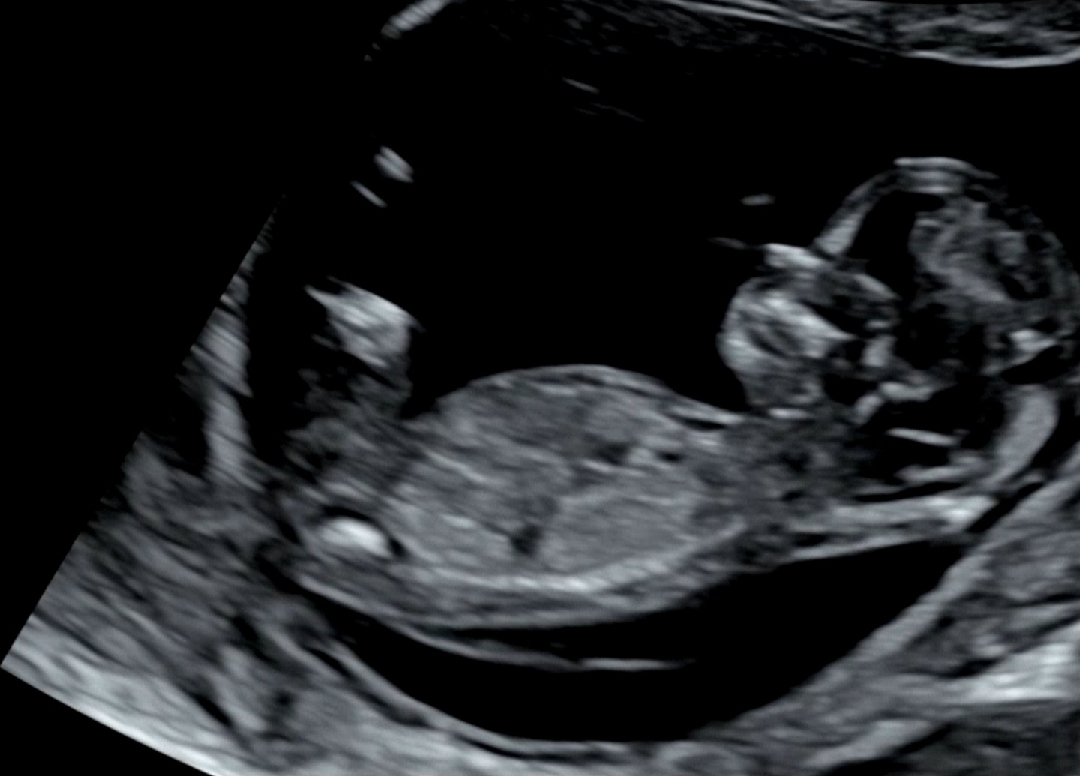

12주1일 각도법 봐주세요

고수님들 도와주세요